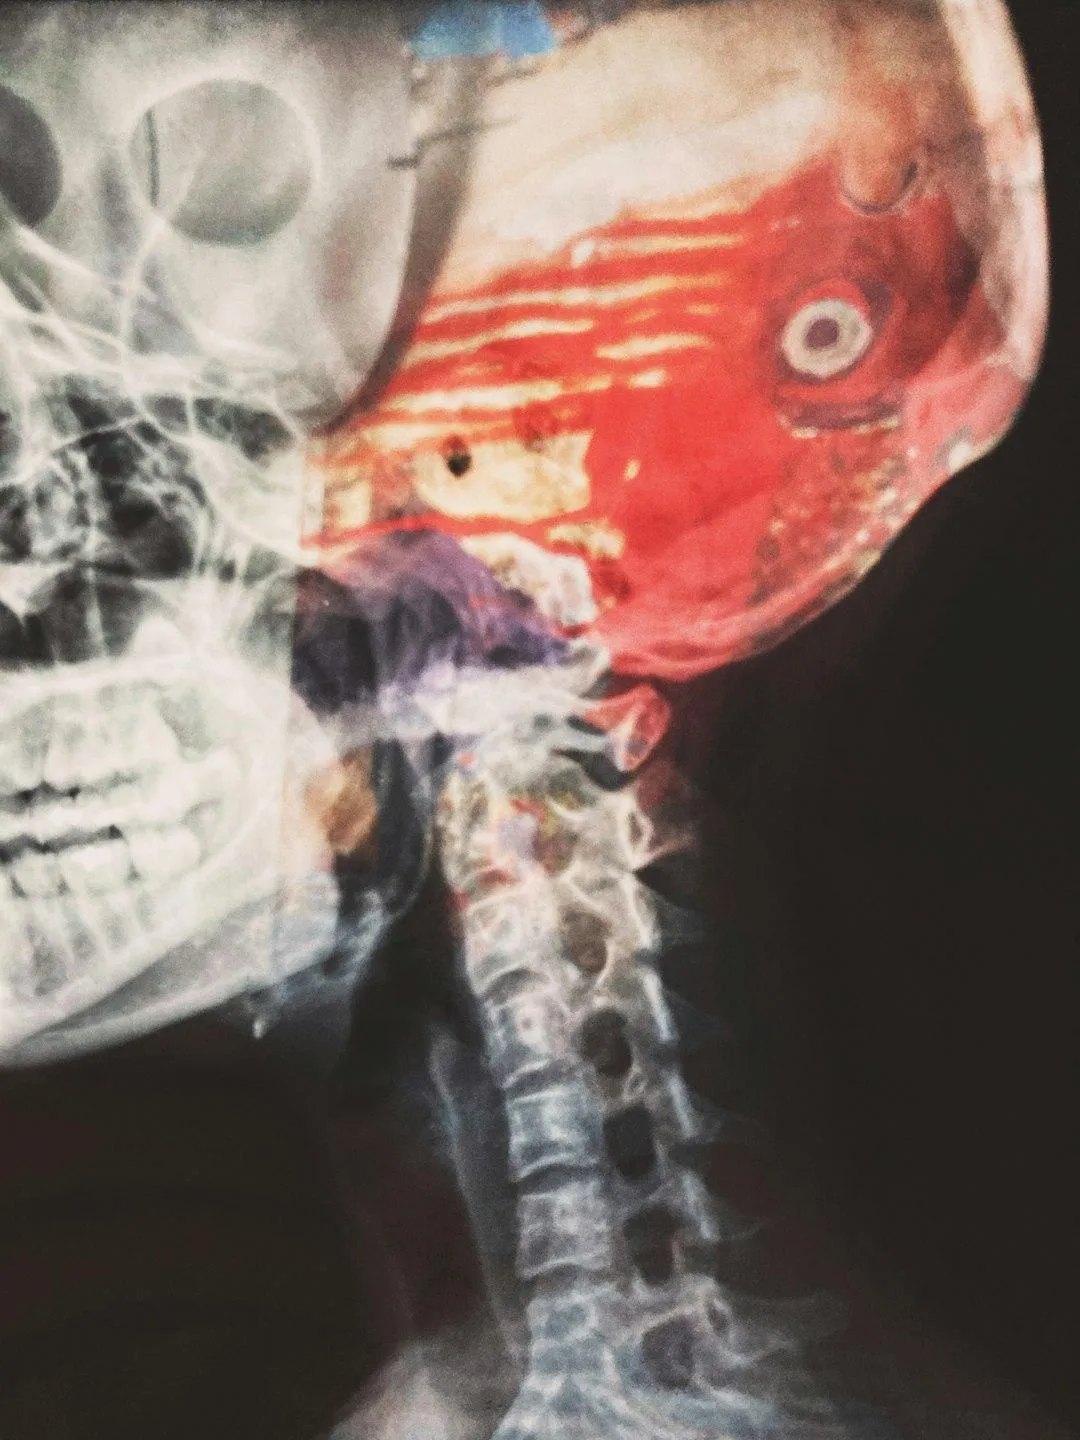

Comprehensive Assessment & Imaging: We evaluate your injury history, symptom timeline (head injury, whiplash, sports impact, etc.), and use specialized imaging to assess subtle misalignments in the atlas/axis region.

Precision X-Rays

Advanced imaging to detect subtle misalignments other scans overlook.

Measurements customized to your exact anatomy.

Clear before-and-after comparisons to verify results.

Precision Imaging: We capture exact alignment of your upper cervical spine to identify misalignments invisible in standard brain-oriented imaging.